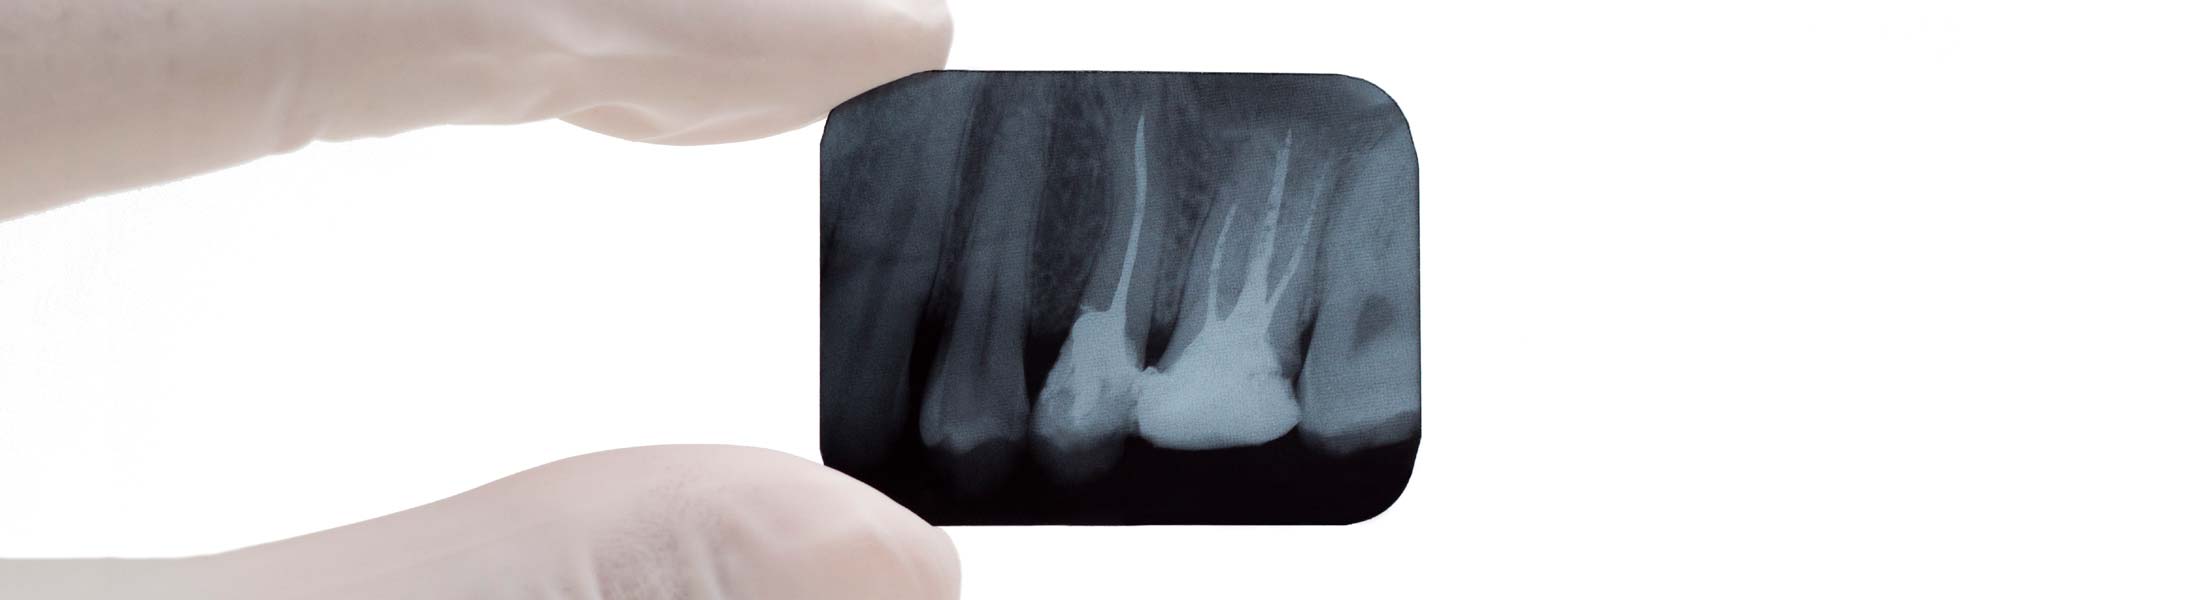

Mit ihr kann ihr Zahnarzt gefährdete Zähne erhalten und retten, die früher in der Regel entfernt werden mussten. Die Wurzelkanalbehandlung ist dabei die wichtigste Therapie – sie ist nötig, wenn das Zahnmark im Inneren des Zahnes (innen = endo) z.B. durch Bakterien entzündet ist. Die Behandlung erfolgt in der Regel beim Zahnarzt.

Trotz einer regelgerecht durchgeführten Wurzelkanalbehandlung kann in manchen Fällen restliche Entzündung an der Wurzelspitze bestehen bleiben. Hier ist eine Wurzelspitzenresektion (WSR) die letzte Möglichkeit der Zahnerhaltung. Mit der Lupenbrille kann die Wurzelspitze sicher gefunden und unter optimaler Sicht präzise und vergrößert dargestellt werden. So können die Entzündung entfernt und die Wurzelfüllungen geglättet werden. Bleibt ein Zahn nach einer erfolgreichen Wurzelspitzenresektion stabil, kann er von dem überweisenden Kollegen für weitere prothetische Maßnahmen verwendet werden.

Bei der Wurzelspitzenresektion mit retrograder Füllung erfolgt die operative Entfernung der Wurzelspitze und Säuberung des Zahnkanals vom Wurzelende aus mit diamantierten Ultraschallspitzen. Danach wird der Wurzelkanal von rückwärts bakteriendicht mit einer Füllung verschlossen. In besonderen Fällen kann diese Behandlung indiziert sein.